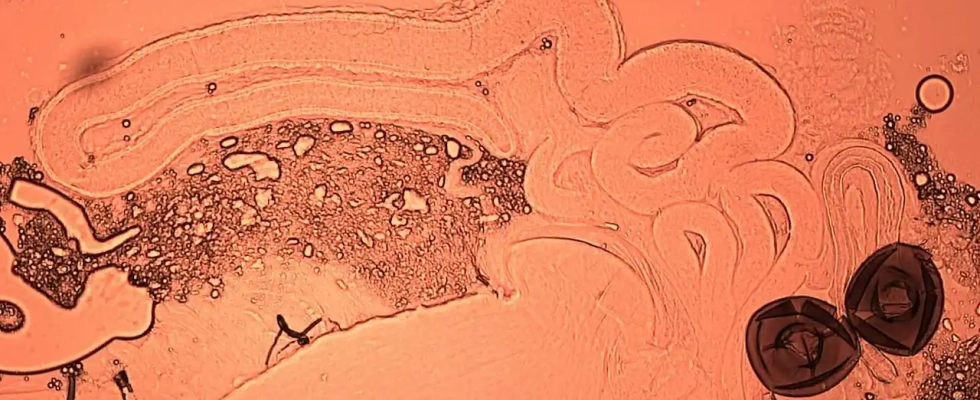

Espermatozoides marcados con proteína fluorescente verde en la espermateca de una mosca de la fruta. Krish Sanghvi

Espermatozoides marcados con proteína fluorescente verde en los testículos y las vesículas seminales de una mosca de la fruta macho. / Krish Sanghvi